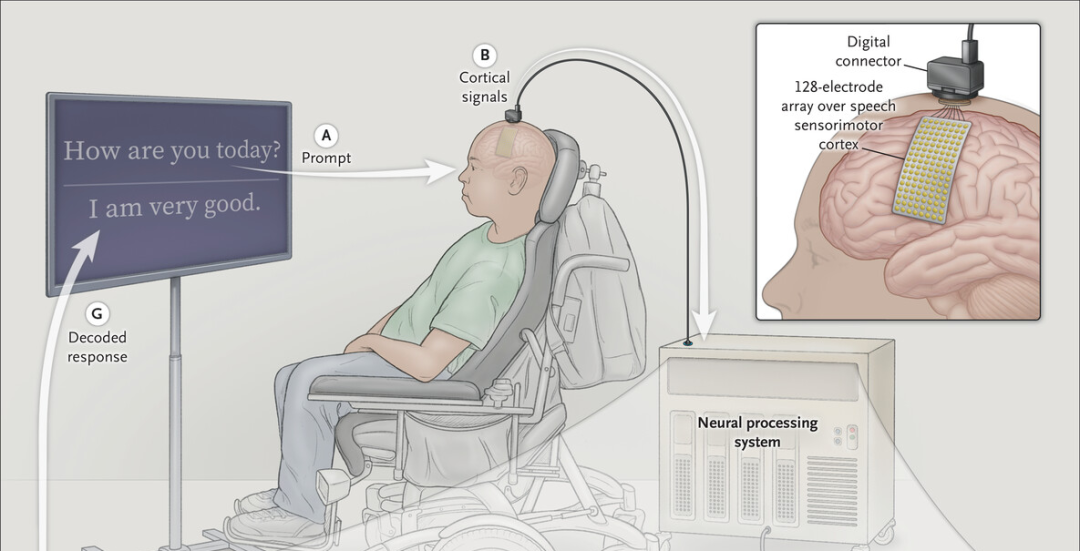

医学影像显示说话时的大脑活动(人工着色)Credit: Zephyr/SPL

这些发现揭示了大脑中语言处理的一些意想不到的方面。先前一些使用非侵入性工具的实验表明,不同的语言会激活大脑的不同部位。但是,作者对直接记录在大脑皮层的信号进行了检查,发现“西班牙语和英语的许多活动实际上来自同一个区域”,Silva说。